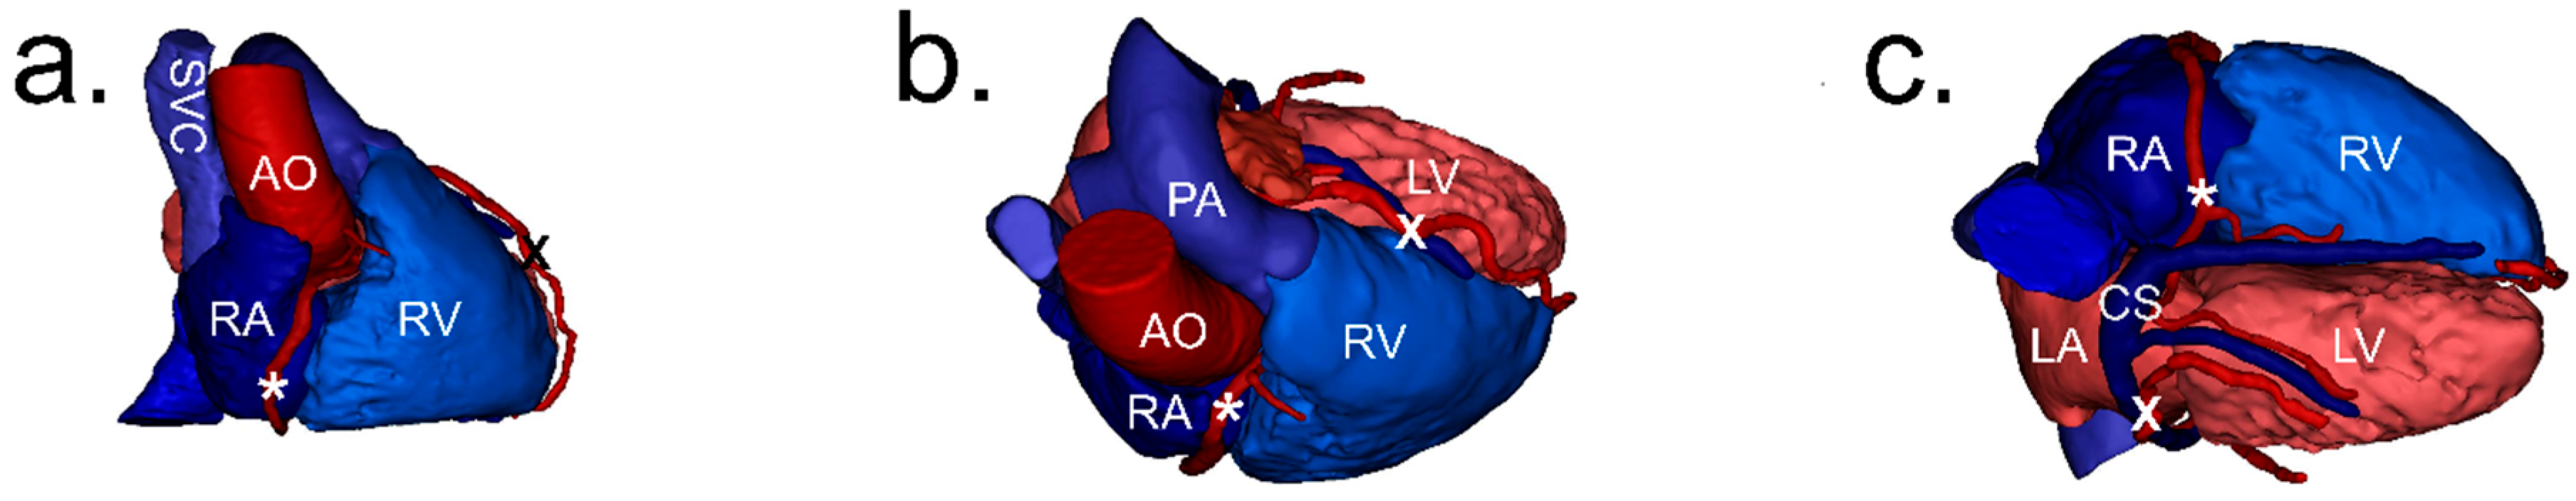

1.1. Anatomy of the Annulus of the Tricuspid Valve

1.2. Clinical Significance of the Region of the Tricuspid Valve Annulus

2.2. Image Processing and Analysis

2.3. Definitions

2.4. Measurements